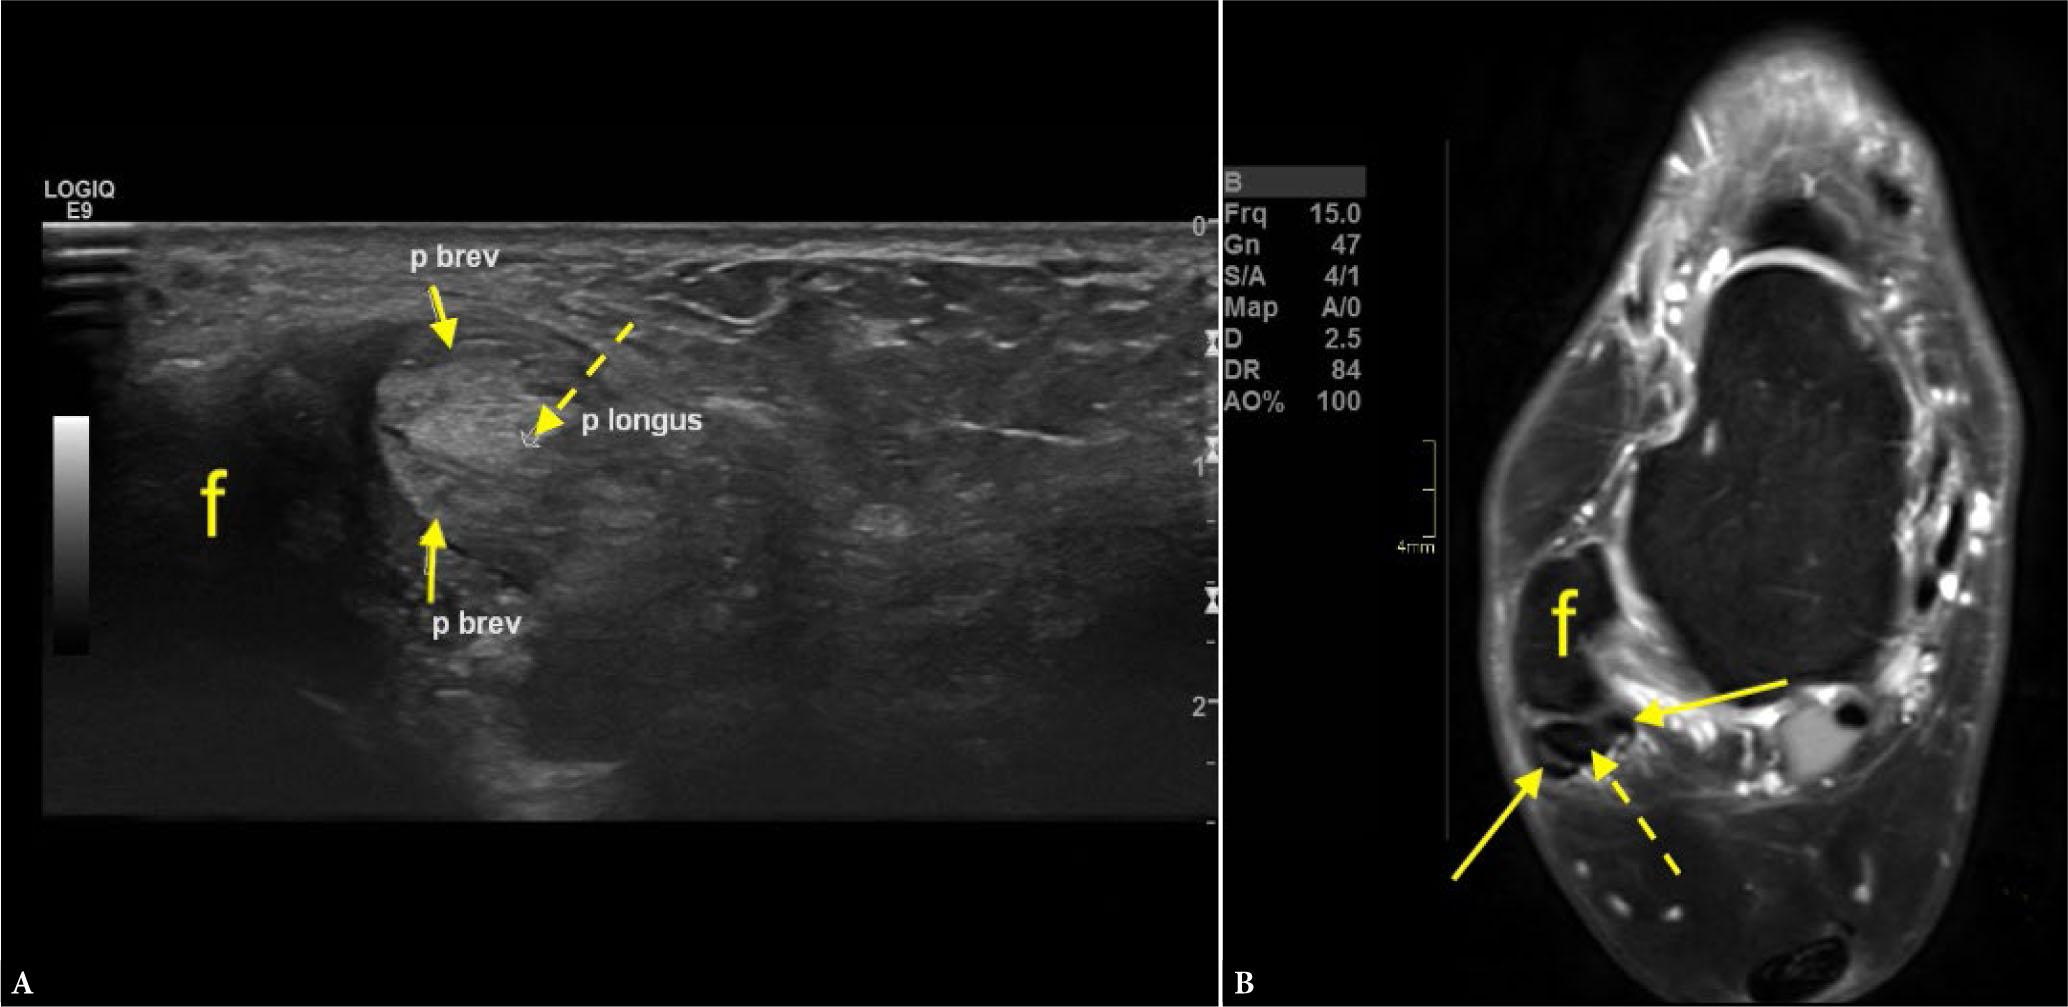

The study cohort consisted of 63 individuals, including 36 women and 27 men, aged 18 to 83 years. The mean age was 50.9 years, with a standard deviation of 16.2 years. MRI was performed in all 63 patients following their ultrasound assessment. Ultrasound examinations revealed a total of 17 split ruptures (20.7% of the patient cohort). Of these, seven cases (11.1%) were false positives (diagnosed on ultrasound but not confirmed by MRI), and nine cases (14.3%) were false negatives (missed by ultrasound but detected on MRI). Six cases (9.5%) were true positives (Fig. 1 and Fig. 2) (identified on both ultrasound and MRI), and 41 patients (65.1%) were true negatives (negative on both modalities).

True positive finding on ultrasound. A 45-year-old patient with pain posterior to the right lateral malleolus for 8 months. Ultrasound (transverse cross-sectional) revealed a peroneus brevis split rupture at the level of the lower half of the lateral malleolus (A). MRI conducted 3 months after the ultrasound confirmed the peroneus brevis split rupture (B. proton density-weighted image with fat suppression). Straight arrows indicate the peroneus brevis split rupture, the dashed arrow points to the peroneus longus, and ‘f ’ shows the lateral malleolus. P brev and p longus refer to the peroneus brevis and peroneus longus